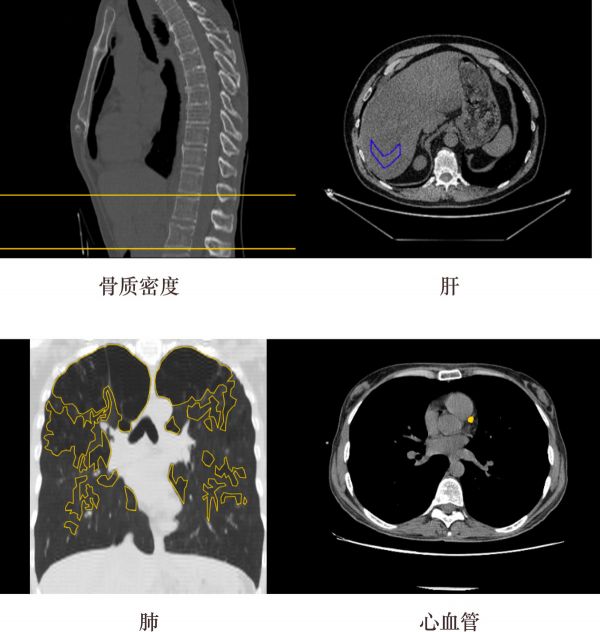

ZEBRA MEDICAL VISION-AI 放射医疗助手

Zebra Medical Vision为放射科医师提供了一个支持AI的助手,其可以接收成像扫描并自动分析它们所研究的各种临床发现。研究结果会传递给放射科医师,以帮助医生做出诊断。链接